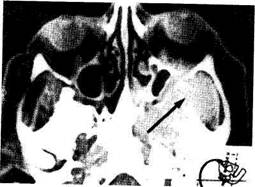

Диагностика. Осуществляется на основании отмеченных симптомов с учетом данных эндоскопического (в том числе с использованием фиброэндоскопа), рентгенологического, а в ряде случаев и ангиографического исследования. При определении распространения опухолевого процесса решающая роль принадлежит КТ и МРТ (рис. 7.4). Дифференцировать юношескую ангиофиброму следует от аденоидов, хоанального полипа, папилломы, саркомы, раковой опухоли, аденомы. Окончательный диагноз устанавливают на основании биопсии, ко-

Рис. 7.4. Компьютерная томограмма черепа больного с юношеской ангиофибромой (указана стрелкой). Прорастание опухоли в глазницу, верхнечелюстную пазуху и решетчатые ячейки.

торая представляет определенные трудности и должна производиться только в ЛОР-стационаре, где имеются все условия для остановки кровотечения.